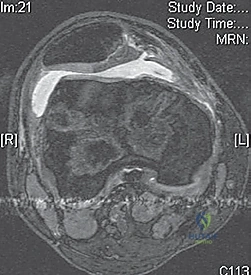

- MRI Scan: Highly recommended for all patients with a large traumatic effusion due to the high rate of occult articular or osteoarticular injury.

* Osteochondral Lesions: Crucial for determining size, location, and potential for repair versus removal.

* Bone Bruise Pattern: Confirms patellar dislocation (medial patella and lateral femoral condyle).

* Anatomical Risk Factors: Assesses patella alta, trochlear dysplasia, tibial tubercle-trochlear groove (TT-TG) distance.

* Bone Bruises: MRI often reveals increased signal on the medial patella and the midportion of the lateral femoral condyle. This distinct pattern helps differentiate it from ACL tears.